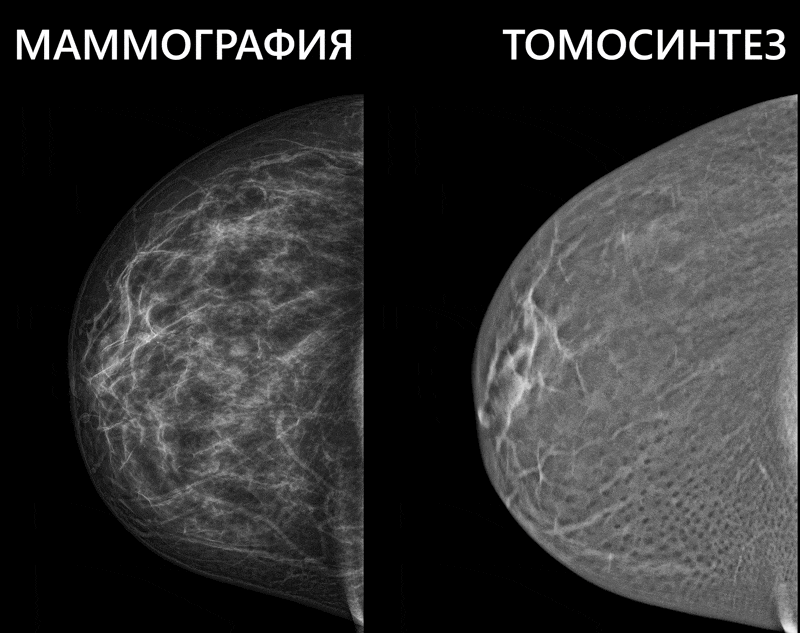

Маммография с томосинтезом

-7

Сегодня это одних из самых точных и информативных методов исследования молочных желез при подозрении на опухоль. Тонкие срезы тканей, которые получает врач, и высокое разрешение самих изображений – комбинация, которая не оставляет шансов раку даже на начальных стадиях. Исследование стоит в 2-3 раза дороже обычной маммографии. Сегодня такую процедуру можно пройти в специализированных диагностических и онкоцентрах на аппарате для маммографии с томосинтензем.